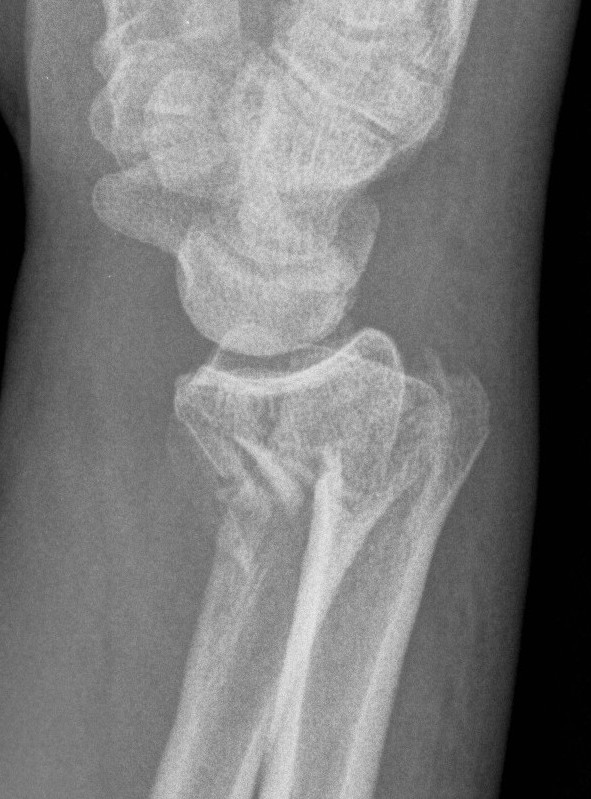

Colle's Fracture

- distal radial fracture with dorsal displacement

Smith's Fracture

- distal radial fracture with volar displacement

- need long arm cast in supination

Volar Barton's

- volar intra-articular fragment

- inherently unstable

- usually need volar buttress plate

Dorsal / Reverse Barton's

- dorsal intra-articular fragment